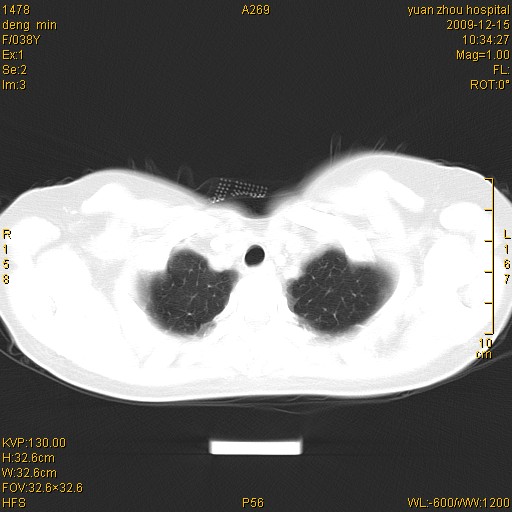

标题: CT23919:F38Y 咳嗽月余 [打印本页]

标题: CT23919:F38Y 咳嗽月余

右肺中下叶、左肺上叶舌段及左肺下叶支气管扩张合并感染。